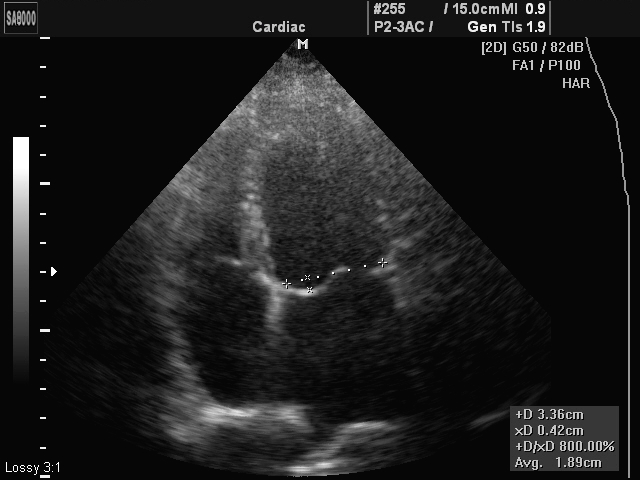

Основным способом выявления «провисания» является прослушивание (аускультация) сердечной мышцы – если есть патология, то можно услышать небольшие щелчки и шум. С помощью данных электрокардиограммы проследить работоспособность митрального клапана невозможно, поэтому для диагностики используется ультразвуковое исследование. С помощью ЭХО удается получить информацию о:

- феномене пролабирования створок;

- количестве крови, которая забрасывается в предсердия (степень регургитации);

- наличии миксоматозной дегенерации тканей.

Во время безболезненной процедуры врач видит на экране монитора четкое изображение митрального клапана и его состояние во время наполнения и выброса крови. В некоторых ситуациях для точного определения наличия или отсутствия деформации части миокарда, пациента просят сделать 10-20 приседаний и потом повторить исследование. Благодаря увеличению артериального давления, приток крови увеличивается, соответственно, можно заметить даже незначительные нарушения. Также с помощью данной методики устанавливается степень провисания.

Также по результатам УЗИ доктор сможет определить и степень нарушения, обратив внимание на величину отклонения от нормы:

- пролапс митрального клапана 1 степени – провисание створок клапана на 3-6 мм;

- 2 степени – провисание его створок на 6-9 мм;

- все, что свыше 9 мм, относится к третьей степени, наиболее тяжелой среди всех существующих.